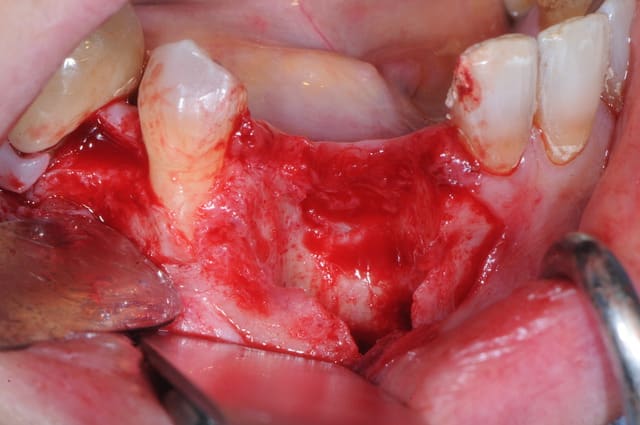

maintenant, la phase reconstruction de la zone antérieure.

1 défaut osseux (y a plus grand chose!)

2 essayage de la membrane titane

3 stabilisation de la membrane

4 comblement osseux

reste plus qu'à attendre...